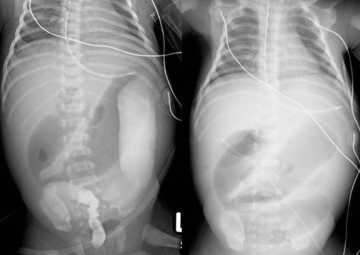

- рентгенография кишечника с контрастом.